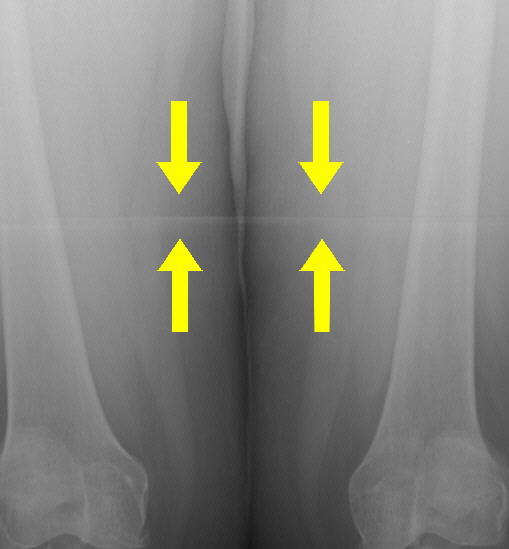

Stitching Artifact

Multiple cassette images stitched together create this artifact.